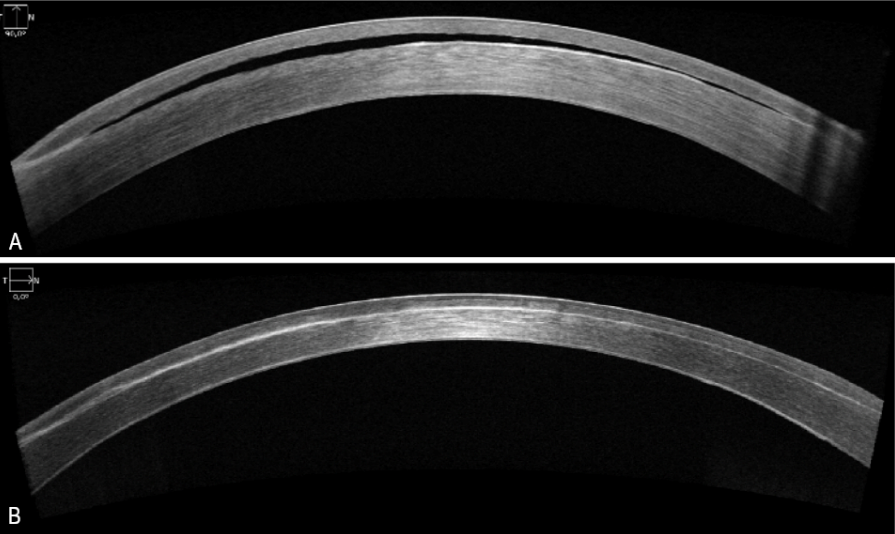

Figure 2: Corneal OCT. A: Corneal OCT showing interface fluid. B: Corneal OCT showing resolution of interface fluid after DMEK surgery

Uneventful Descemet membrane endothelial keratoplasty (DMEK) surgery was performed with a marked postoperative increase in visual acuity (Snellen 0.5, 3 months postoperative). OCT of the cornea 2 months after surgery showed complete resolution of the interface fluid pocket with complete attachment of the Descemet membrane (Figure 2B [Fig. 2]). Three months after surgery, epithelial ingrowth in the interface was noticed (Figure 1B [Fig. 1]). This epithelial ingrowth did cause irregular astigmatism observed with Scheimpflug imaging (Figure 3 [Fig. 3]). However, as her visual acuity was significantly improved, the patient preferred a watchful waiting approach as she had already undergone a myriad of eye surgeries in the past few years.